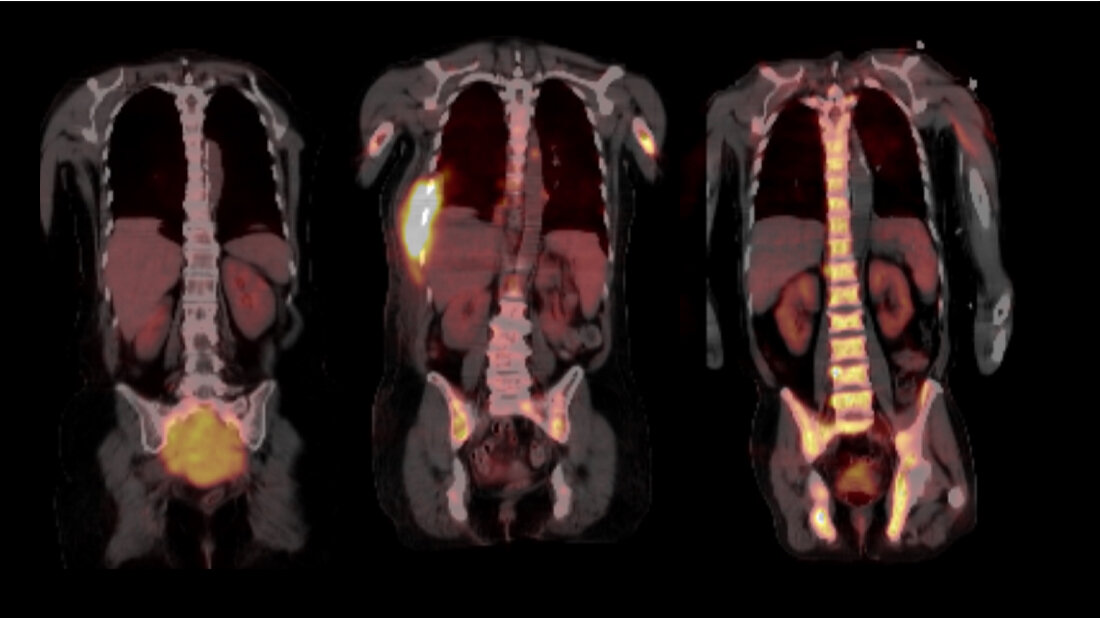

Ihre Arbeit basiert auf Proben aus dem weltweit größten Myelom-Zentrum an der University of Arkansas for Medical Sciences in Little Rock (USA), wo beide Wissenschaftler mehrere Jahre lang gemeinsam geforscht haben. Im Jahr 2017 hatten sie bereits über die räumliche, genomische Heterogenität der Tumorzellen berichtet. „Bis vor kurzem wurden in der Forschung immer nur einzelne Knochenmarkproben aus dem Becken untersucht. Ein erwachsener Mensch verfügt jedoch über etwa fünf Kilogramm Knochenmark, die sich über das gesamte Skelettsystem verteilen. Somit ließ sich die Evolution der Tumorzellen bislang gar nicht ausreichend abbilden“, schildert Privatdozent Dr. Leo Rasche, Erstautor der Studie und Juniorgruppenleiter am Mildred-Scheel-Nachwuchszentrum (MSNZ) für Krebsforschung am Uniklinikum Würzburg die Ausgangslage. Die Forscher und ihre Teams haben nun 140 Proben analysiert, die in einem Zeitraum von bis zu 13 Jahren aus verschiedenen Skelettlokalisationen von 24 Myelom-Patientinnen und -Patienten gewonnen wurden. Dazu wurden zum Teil bildgebende Verfahren wie Magnetresonanztomografie (MRT) und Positronen-Emissions-Tomografie (PET) genutzt, um die Tumorherde, die so genannten fokalen Läsionen abzubilden.

Durch die Nutzung der bildgebenden Verfahren kamen die Wissenschaftler zur ersten wichtigsten Erkenntnis: Dass die entscheidenden Schritte der Tumor-Evolution oft außerhalb des Beckens, in den Tumorherden ablaufen. „In den fokalen Läsionen haben wir Mutationen gefunden, die wir sonst nirgendwo gesehen haben und die aggressiver erschienen, da sie in die Kategorie der so genannten Cancer Driver Genes - genetische Veränderungen, die das Krebswachstum ankurbeln - fielen. Die Eigenschaften der Tumorzellen können sich jedoch nach jeder Therapie-Linie unterscheiden, sogar dann, wenn sich die Tumormasse während der Therapie nicht verändert hat. Wir schließen daraus, dass regelmäßige biologische Untersuchungen des Myeloms während der Therapie erfolgen müssen, wenn die Erkrankung gezielt behandelt werden soll“, resümiert Niels Weinhold, Leiter der Translationalen Myelom-Forschung am Universitätsklinikum Heidelberg.

Generell sei bei allen Behandlungen, auch nach vermeintlich erfolgreicher Therapie, eine regelmäßige Untersuchung vonnöten. „Wir bitten unsere Patientinnen und Patienten auch in der Remission alle drei Monate zu uns, um eine Kontrolle im Blut durchzuführen und gegebenenfalls mittels MRT oder PET zu prüfen, ob es fokale Läsionen gibt“, schildert Rasche. Unbehandelt versterben die Betroffenen in der Regel innerhalb eines Jahres.